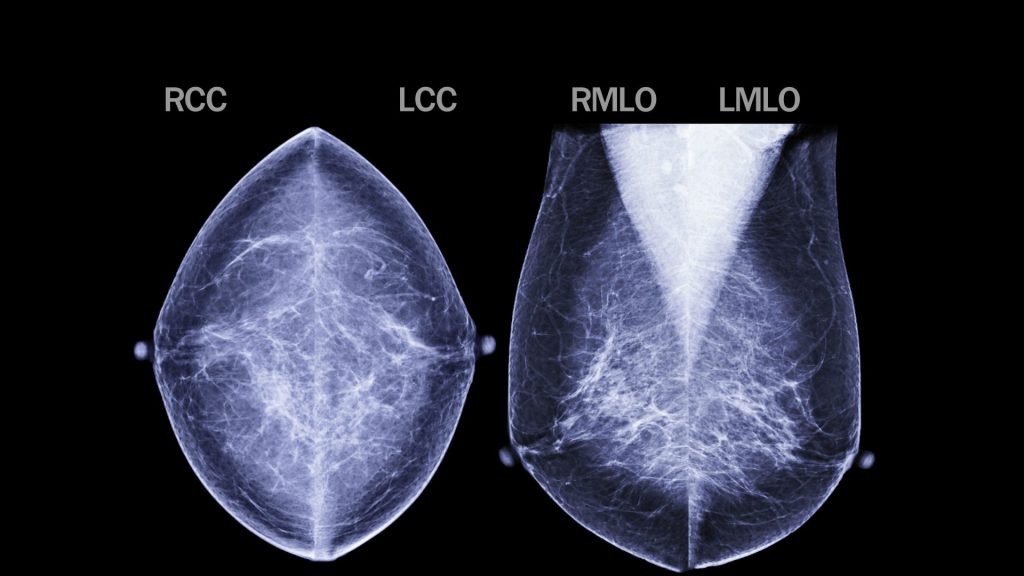

Breast Cancer Research Paper Recognized by National Cancer Institute

Posted on March 20, 2025 by Inbox Army

Posted in School & Program UpdatesTagged U of Florida, For Friday Letter March 21 2025